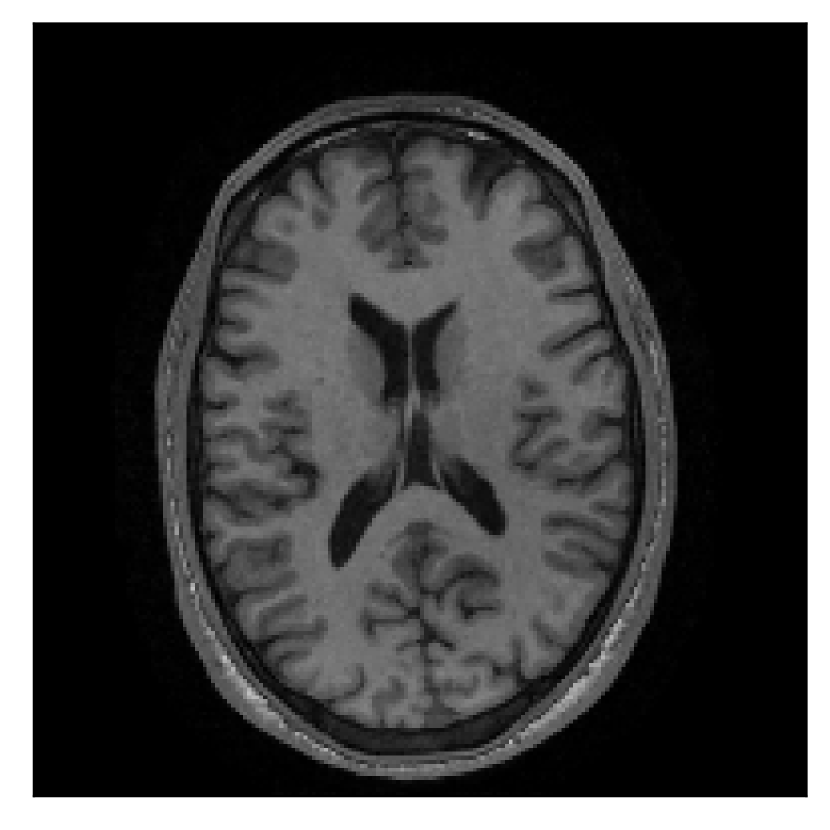

| Section 3.3, Figure 12 | Sagittal | 22.26 | 27.54 | 0.6963 | 0.8409 |

| Coronal | 23.46 | 31.65 | 0.7321 | 0.8370 | |

| Axial | 24.55 | 32.33 | 0.7895 | 0.8144 | |

The motion-corrected full-volume scans were analyzed by a neuroradiologist with 16 years of experience. These were generally deemed of good radiological quality. The motion-related artifacts have been completely removed, and the results are quite close to the ground truth. In Table 3, we organized a more detailed qualitative analysis of the 3D results, geared toward a radiological assessment of the corrected scans.

| Experiment | Contrast | Motion resolution | Blurring | Artifacts | Additional comments |

| Section 3.3, Figure 12 | T2 | Completely corrected | No blurring | No additional artifacts | |

4.3 Experiment 3: scanner reconstruction vs raw k-space data

The results of the two experiments described in Section 3.3 are depicted in Figures 12 and 14. The main difference between the two experiments is related to the input data for the proposed motion-correction algorithm.

In the first experiment, the corrupted contrast has been acquired with a protocol based on a linear filling pattern in -space. Note that, in this particular case, the scanner reconstruction implements the SENSE method. We then extracted the DICOM of both amplitude and phase produced by the scanner, and used it as input data (after a Fourier transform) for the algorithm. The proposed scheme is able to successfully remove the motion artifacts in Figure 12.

A significant part of our experimentation was devoted to assess whether the scanner reconstruction (available as DICOM format) can be directly used as input data for the proposed correction method (Section 4.3). We established that the scanner reconstruction is not suitable for this purpose when it is obtained via compressed-sensing algorithms (Appendix A), which is the case for randomized sampling on the 1.5 T Philips Ingenia scanner utilized in this work. In this case, we must resort to the raw -space data and perform an intermediate SENSE reconstruction for effective motion correction.